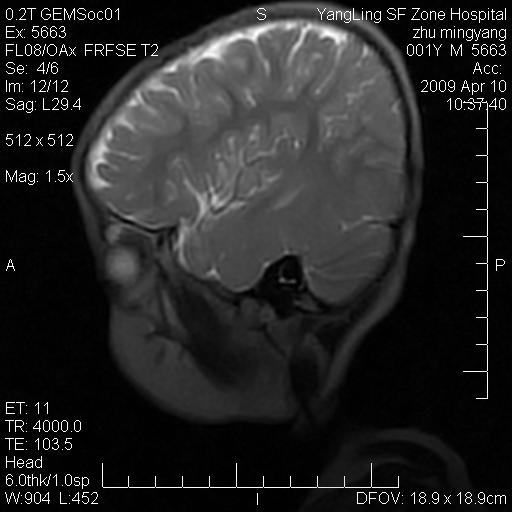

患者:1岁半,两天前外伤收住我院,ct检查小脑占位

考虑星形细胞瘤,建议增强

髓母细胞瘤或血管母细胞瘤,增强后可以鉴别;影像资料见 <。鱼博浪老师的《中枢神经系统ct与mr鉴别诊断》 小脑部肿瘤章节。

髓母细胞瘤或血管母细胞瘤!支持!

支持考虑髓母细胞瘤

考虑----髓母细胞瘤可能性大

考虑髓母细胞瘤或室管膜瘤。

支持髓母细胞瘤。

考虑髓母细胞瘤。

考虑髓母细胞瘤或星形细胞瘤

考虑髓母细胞瘤.

考虑髓母细胞瘤可能性大。

小脑肿瘤.考虑髓母细胞瘤可能.

就病灶部位及临床资料首先考虑髓母.